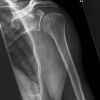

Schulter lateral (medizinisch)

Technik

• FDA: 1,15 m

• Ausgangsformat: 18/24 quer

• mit Raster

Indikation

entzündliche und degenerative Veränderungen, Kalkablagerungen der Rotatorenmanschette

Lagerung

sitzend/ stehend am Rasterwandstativ

OA um 90° angehoben

Ellenbogen um 90° angewinkelt

Handinnenfläche zeigt zum Kopf

Zentralstrahl

Querstrahl: mittig durch den OA

Längsstrahl: Gelenkspalt

Einblendung

oberes Licht 2 QF über Schulter-Haut-Grenze

Bemerkung

Aufnahme auch im Liegen möglich